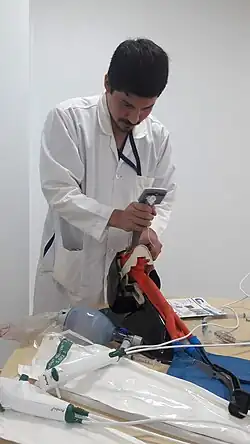

Tracheal Intubation

Tracheal intubation involves the placement of a tube, known as an endotracheal tube, into the mouth or nose. Intubation first begins with the use of anesthesia medications, usually delivered through an IV, to place the patient to sleep. Next, extra oxygen is administered to the patient through a face mask. Once the patient is asleep, an anesthesia provider will tilt the patient's head back and insert a viewing device, also known as a laryngoscope, into the patient's mouth. The laryngoscope is accompanied by a dull blade to help move other oral structures, such as the tongue, out of the way. Once the anesthesia provider identifies the epiglottis, which covers the larynx, the epiglottis is manually lifted using the laryngoscope.[8] The endotracheal tube is inserted through the larynx past the vocal cords and secured by inflating a small balloon at the end of the endotracheal tube. Once secured, the laryngoscope is removed. The tube is then secured at the mouth, often using tape or with a strap that wraps around the patient's head. Finally, correct placement is verified by listening to both lungs for breath sounds.[1]